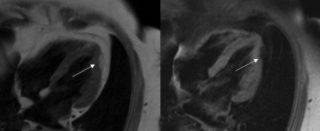

Gli strumenti di elezione per la diagnosi sono i test di imaging, inclusa l’ecografia bidimensionale, l’angiografia e la risonanza magnetica, che rivelano le anomalie strutturali e funzionali. La mappa elettroanatomica permette di individuare le aree a basso voltaggio corrispondenti a un’atrofia del miocardio, con sostituzione grasso-fibrosa.